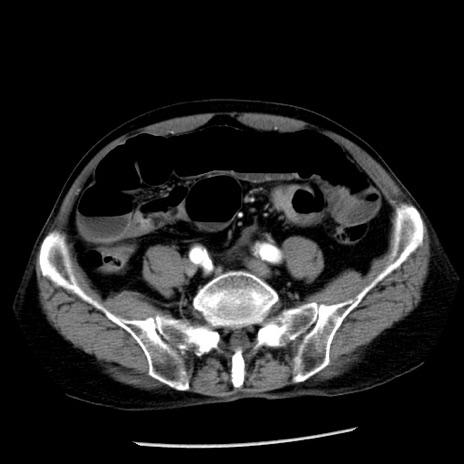

症例26(横断像)

【症例】80歳代男性

【主訴】嘔吐

【現病歴】昨晩2回嘔吐あり、今朝になっても嘔吐あり。来院。

【既往歴】胃潰瘍

【身体所見】意識清明、BT 37.6℃、BP 166/95mmHg、HR 100bpm、SpO2 97%、腹部:平坦・軟、腸蠕動音聴取良好、圧痛なし。

【データ】WBC 21900、CRP 1.46